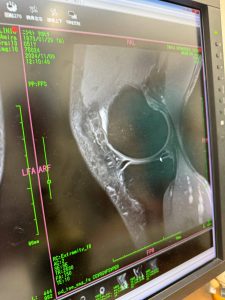

結果は、半月板損傷水平断裂とのことでした。

おまけに水も溜まっているとか(涙)